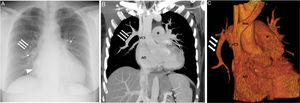

Presentamos un caso de DVPAP diagnosticado incidentalmente en una tomografía computarizada (TC) de tórax en una mujer de 51 años, asintomática. En la TC se observó un DVPAP del lóbulo superior derecho, del lóbulo medio y de algunos segmentos del lóbulo inferior derecho a la vena cava superior, que condicionaba una dilatación de cavidades cardiacas derechas y signos de hipertensión pulmonar precapilar (fig. 1B y C). Nuestro caso resulta interesante por la edad de presentación (a pesar de un DVPAP significativo) y la ausencia de una comunicación interauricular tipo seno venoso concomitante. De forma consensuada se decidió actitud expectante dada la buena función biventricular y la ausencia de síntomas.

A) Radiografía de tórax (proyección posteroanterior) en la que se observa un crecimiento de la aurícula derecha (punta de flecha), un aumento del tamaño y de la densidad de ambos hilios (flechas curvas); nótese la presencia de una estructura tubular en pulmón derecho (flechas rectas). B y C) Imágenes de reconstrucción coronal MIP (proyección de intensidad máxima) (B) y 3D (C) en las que se confirma la existencia de un drenaje de la vena lobar superior derecha a la vena cava superior (flechas rectas). Además el retorno venoso del lóbulo medio y de varios segmentos del lóbulo inferior derecho también drenaba en dicha estructura tubular. Se observan signos de hipertensión pulmonar precapilar con aumento del calibre del tronco de la arteria pulmonar (asterisco) y crecimiento secundario de la AD. AD: aurícula derecha; Inn: vena innominada; VCS: vena cava superior; VD: ventrículo derecho.